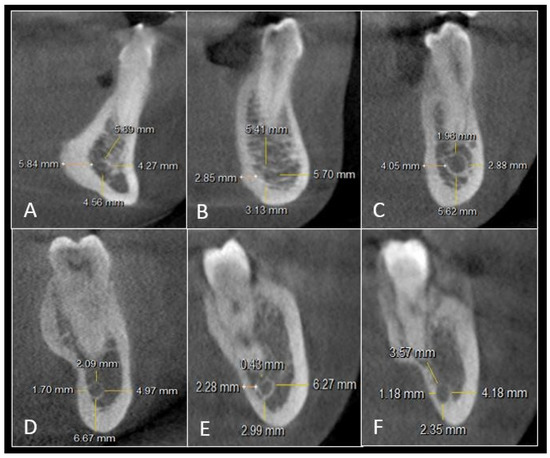

2.2. Imaging Analysis

| Teeth | Right Side | Left Side | |||||||

|---|---|---|---|---|---|---|---|---|---|

| LCP | BCP | Inferior Border of Mandible | Root Apex | LCP | BCP | Inferior Border of Mandible | Root Apex | ||

| Canine | 5.6 | 4.8 | 8.9 | 3.5 | 5.4 | 4.9 | 9.1 | 3.5 | |

| PM-1 | 3.4 | 4.5 | 8.7 | 4.7 | 3.4 | 4.3 | 8.7 | 4.6 | |

| PM-2 | 3.1 | 3.7 | 8.4 | 4.4 | 3.4 | 3.6 | 8.4 | 4.1 | |

| M-1 | Mesial root | 2.9 | 4.9 | 7.6 | 4.4 | 2.9 | 5.2 | 7.4 | 4.1 |

| Distal root | 2.6 | 4.7 | 7.2 | 4.8 | 2.7 | 4.6 | 7.5 | 4.6 | |

| M-2 | Mesial root | 2.5 | 5.9 | 6.2 | 4.2 | 2.2 | 5.7 | 5.9 | 4.1 |

| Distal root | 2.4 | 5.4 | 6.4 | 3.6 | 2.1 | 5.8 | 6.1 | 3.6 | |

| M-3 | Mesial root | 1.8 | 4.3 | 2.4 | 3.8 | 1.7 | 4.7 | 2.7 | 3.7 |

| Distal root | 1.2 | 4.1 | 2.1 | 3.9 | 1.2 | 3.9 | 2.6 | 3.8 | |